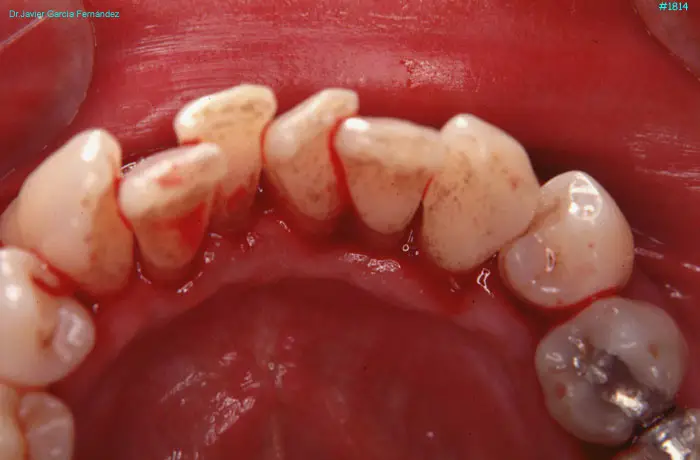

image 80